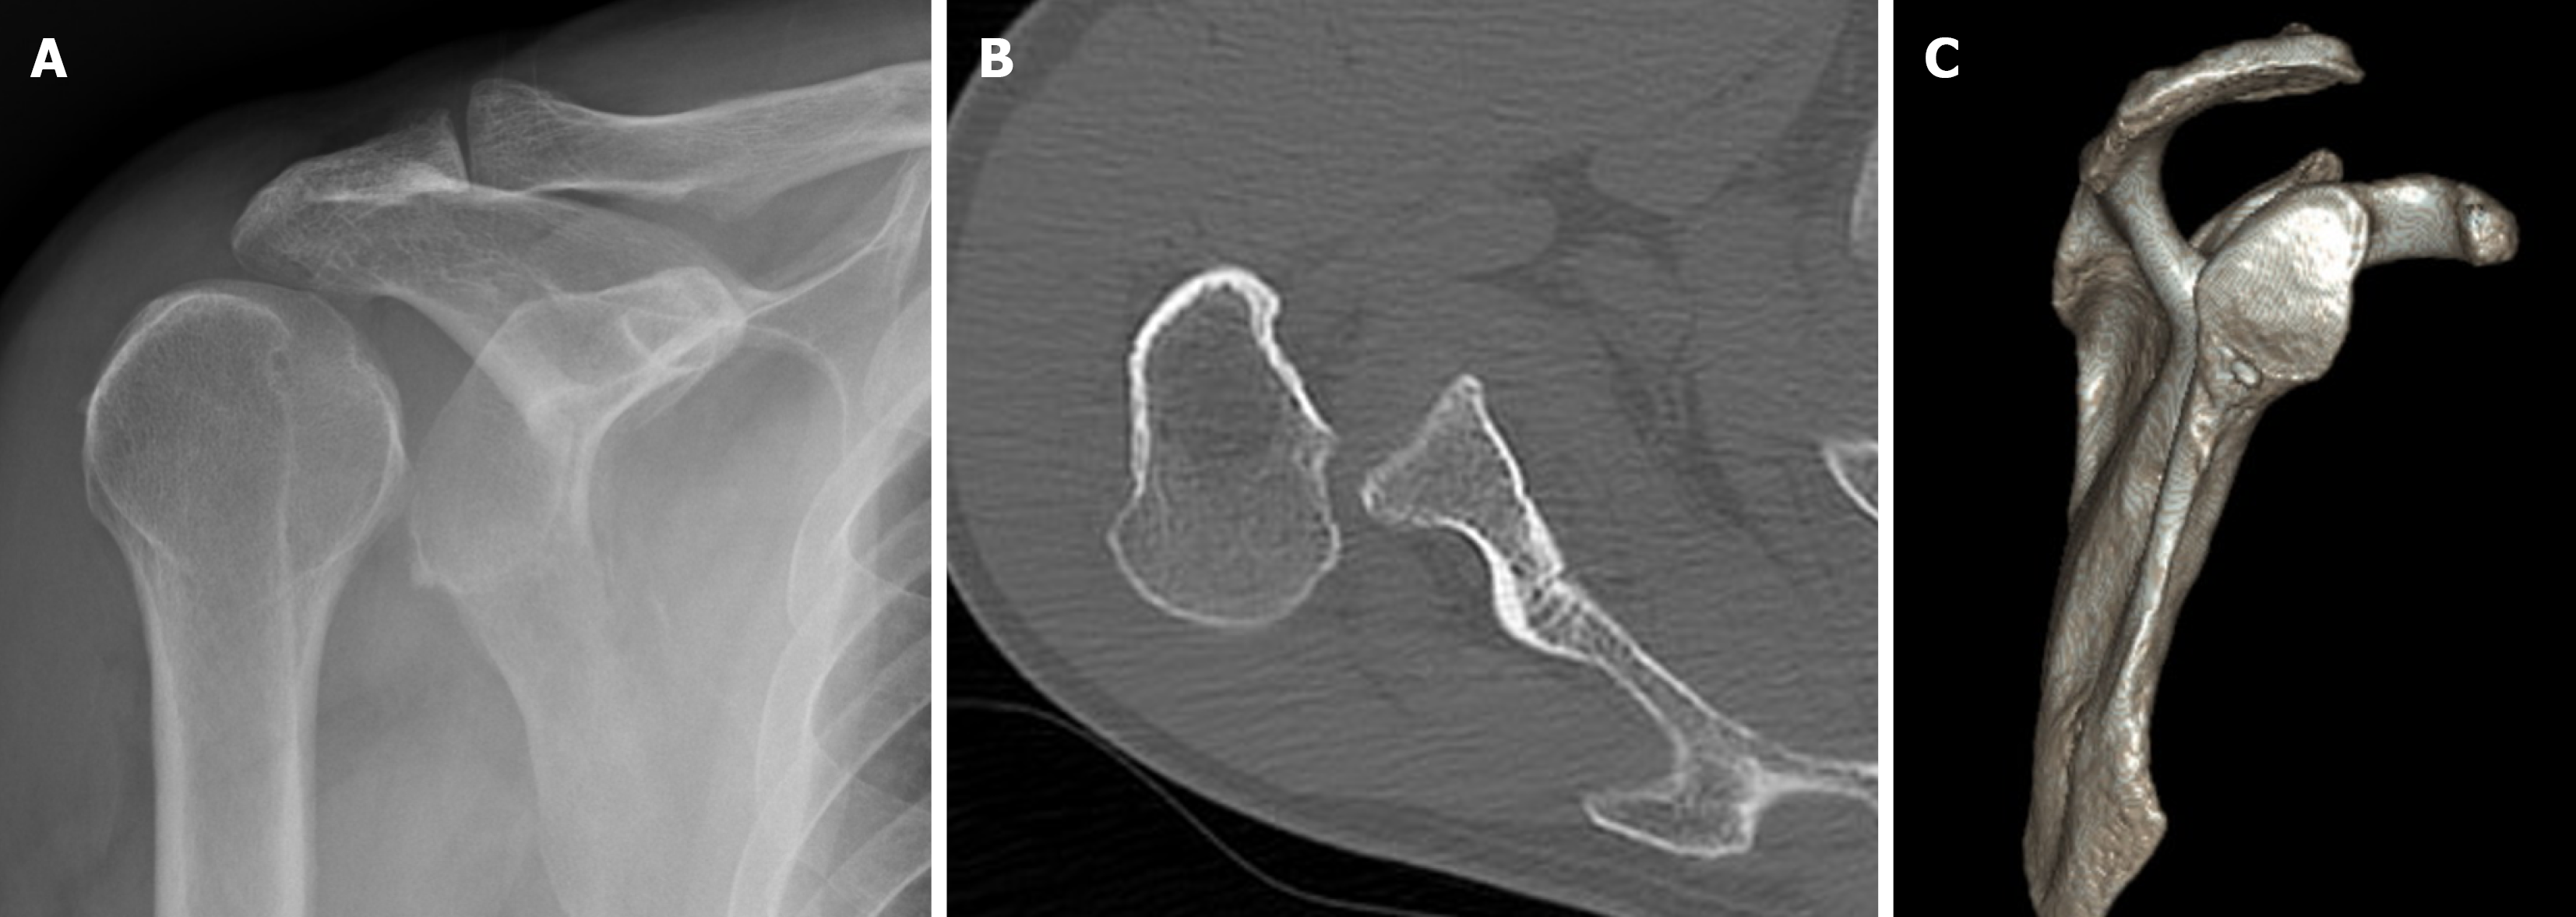

Figure 1 Imaging findings of posterior shoulder dislocation.

A: The lightbulb sign and loss of the normal half-moon overlap on the right shoulder indicated posterior dislocation; B and C: Computed tomography revealed posterior shoulder dislocation with minimal glenoid bone loss (< 10%).